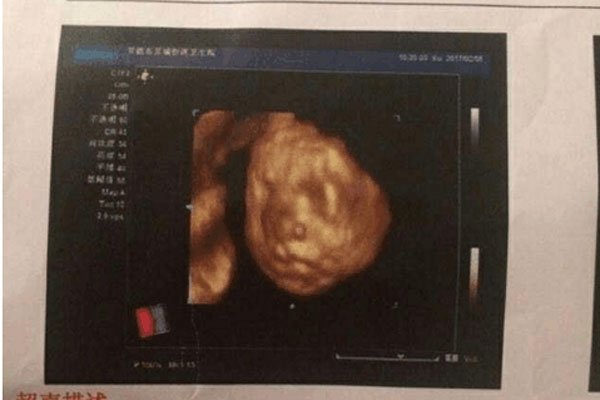

无法判定孩子性别的时候,一些人就会把十男九漏这种事情当做判定自己生的是不是男孩儿的标准,其实从医学的角度来看,根本不存在所谓的十男九漏,一般来说十男九漏的现象会发生在孕早期,早期孕妇出血分多种情况,如果出血的血液,呈现出咖啡色,那么就没什么事情,不用太过担心,这只是氧化的缘故,说明出血已经停止,只要多注意休息,不要过度运动就可以了。

但是如果孕妇出血一直都是鲜红色的,那么一定要注意了,会发生这种情况一般是因为怀孕初期胚胎着床不稳定,出现这种情况并不代表是流产,只能说流产的几率比较大。第二种可能性是宫外孕,孕妇在6-7周时,用超声波还未看到胚胎,但是却有出血的症状,并且人类绒毛膜激素偏高时,这很可能就是宫外孕的情况,孕妈妈要注意伴随出血的同时是否有下腹疼痛的情况发生,有的话要立即就医。